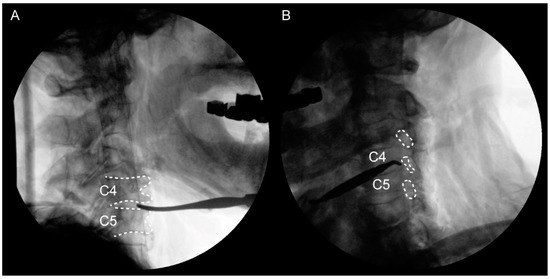

The selected cadavers were confirmed to present foraminal stenosis upon oblique viewing by mobile C-arm with 12-inch image intensifier (Ziehm Vision; Ziehm Imaging GmbH, Orlando, FL, USA). This condition could increase the likelihood of C4-5 being pinched in the extradural and extraforaminal zone. Therefore, PC5P might be induced by pre-existing C4–5 foraminal stenosis. In addition, this would make it easier to observe stretching of the nerve root [4,8]. Dissection was performed on the left side of the neck of each cadaver. First, using the Smith–Robinson approach [17], we identified the anterior vertebral body. Sternocleidomastoid muscles (SCMs) were cut at the proximal site, so that the C5 and C6 roots from the anterior scalene could be seen. The distal part was dissected up to the supraclavicular area (to the brachial plexus’ superior trunk) while preserving other structures (Figure 1). To confirm the C5 and C6 roots, C-arm was used to locate the C4–5 and C5–6 foramen (Figure 2). The dissection was performed by two orthopedic surgeons, with a main operator with over 20 years of experience in thousands of cases of anterior cervical spine surgery and an assistant with 2 years of experience in hundreds of cases.

Figure 2.

(A) Lateral view to confirm the C4–5 disc. (B) Oblique view to confirm the C4–5 foramen. The C4–5 foramen is narrower compared to the adjacent level.